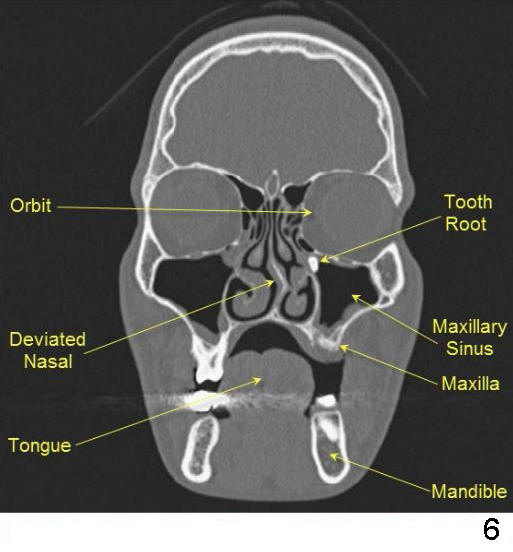

上颌窦(Maxillary sinus,图一)是头面部最大一对副鼻窦,位于上牙上方(图二,三),它大小不一,往前可达侧切牙,后面抵达上颌骨后缘。

上颌窦开口高(Orifice(图四)(Ostium,图九) of maxillary sinus),上颌窦腔(图五:Antrum)有粘膜(Membrane)覆盖,分泌鼻涕。开口可被异物(包括牙根 (Tooth Root),图六),上颌窦提高术植骨(图七))阻塞。植牙,植骨最好不要接近上颌窦内侧,避免阻塞或者创伤上颌窦开口。开口阻塞造成分泌物滞留(图八:Fluid collected in sinus),感染。开口狭窄手术由图九右侧显示。